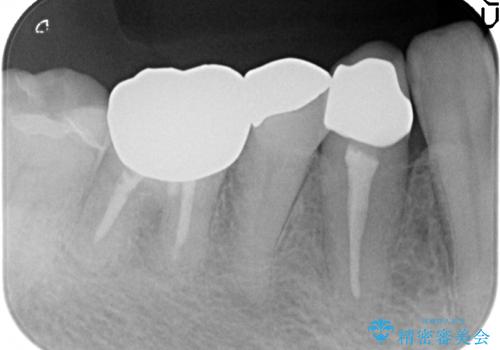

- 他院にて右下4番目の歯の再根管治療が必要だと言われた方の症例です。

再根管治療終了後、オールセラミッククラウンによる補綴を行いました。

今回用いたオールセラミッククラウンは、ジルコニアフレームという白い素材の上にセラミックを盛っているため審美性が非常に高いのが特徴です。

またジルコニアは人工ダイヤモンドの材料にも使われているほど高い強度を持っており、そのためオールセラミッククラウンは審美性だけでなく、奥歯やブリッジの補綴も可能とするクラウンです。